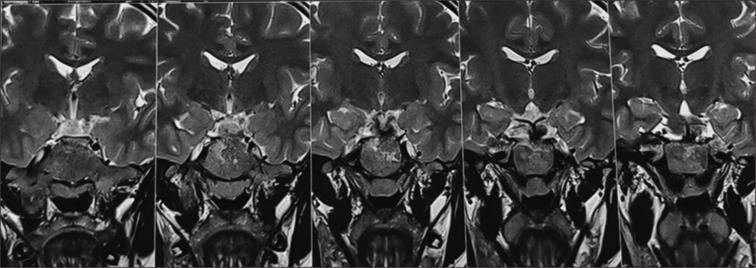

McCune-Albright syndrome is a rare and challenging disorder characterized by a triad of cutaneous, bone and multiple endocrine abnormalities. We present the case of a 15-year-old female with varied symptoms including precocious puberty, prolactinoma, polyostotic fibrous dysplasia, and hyperthyroidism. On examination, she had a palpable nodule in the right lobe of the thyroid with an atrophic left lobe on ultrasonography. Thyroid scan in this patient posed a diagnostic challenge which was resolved with additional single-photon emission computed tomography/computed tomography (SPECT/CT). On SPECT/CT, she was diagnosed with autonomously functioning thyroid nodule and treated with 15 mCi of 131I.